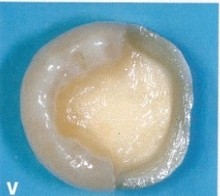

(上图嵌体预备少,保留更多自己的牙体组织,龈上肩台)

2、边缘位于龈上自洁区,可高度抛光,不易附着菌斑,易清洁,利于牙周组织的健。

(上图形成完美的边缘密合,防止术后酸痛)